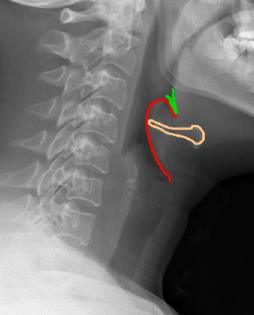

This is a lateral radiograph of the neck, which is sometimes done prior to other more definitive studies to look at the airway.

In Image A from our patient, the hyoid bone is shown in orange, and a very thick and inflamed epiglottis in red. The region of the valleculae is shown in green. This is an emergency, as epiglottitis can lead to complete airway obstruction. Image B is a comparison study to show the normal appearance of the epiglottis.